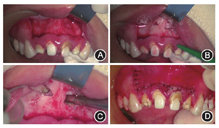

显微根尖手术再治疗:4%阿替卡因局部浸润麻醉,消毒铺巾,自

远中纵切口,

龈缘下方约5 mm扇形水平切口,翻起黏骨膜瓣,可见

根尖区骨质缺损,搔刮肉芽组织,切除根尖约2 mm。

根尖未见明显骨质缺损,去骨,搔刮肉芽组织,切除根尖约3 mm。对根尖行亚甲蓝染色,显微镜下观察未见明显裂纹。超声工作尖进行根管倒预备,三氧化矿物凝聚体(mineral trioxide aggregate,MTA)(Dentsply,美国)倒充填。组织瓣复位,6-0号线缝合,1周拆线。治疗过程见图6。

显微根尖手术再治疗过程 A:龈缘下方扇形水平切口,翻开组织瓣;B:

根尖切除后;C:使用三氧化矿物凝聚体根尖倒充填后检查;D:手术切口缝合

根尖切除后;C:使用三氧化矿物凝聚体根尖倒充填后检查;D:手术切口缝合术后根尖X线片显示